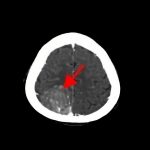

断層撮影